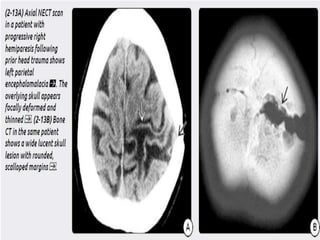

 Later-stage GSFs demonstrate a progressively

widening and unhealing fracture. A lucent

skull lesion with rounded, scalloped margins

and beveled edges is typical.

 Stage IIIGSFs can cause pronounced skull deformities and progressive neurologic deficits if left untreated.  Later-stage GSFs demonstrate a progressively widening and unhealing fracture. A lucent skull lesion with rounded, scalloped margins and beveled edges is typical.  the middle cranial fossa is most susceptible because of its thin "squamous“ bones and multiple foramina and fissures.

Axial bone CT in a

patient who was hit in the

head with a falling ladder

shows an extensively

comminuted, depressed skull fracture.